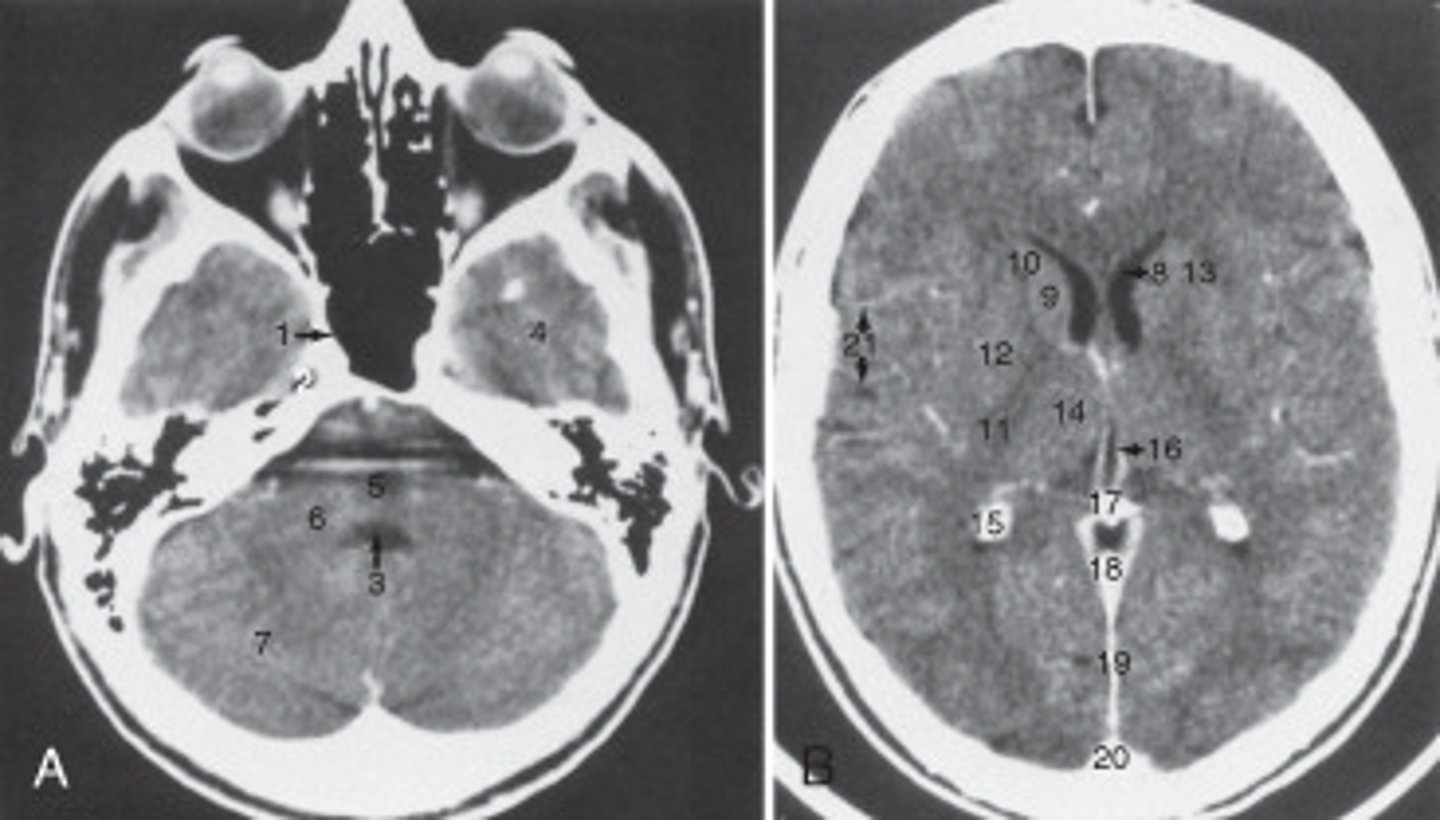

The anterior (frontal) horn of the lateral ventricle is labeled as:

<p>The anterior (frontal) horn of the lateral ventricle is labeled as:</p>

The thalamus is labeled:

<p>The thalamus is labeled:</p>

19

the fall cerebri is labeled:

calcified choroid plexus

The structure labeled 15 is the:

fourth ventricle

The structure labeled 3 is the:

cerebellar hemisphere

The structure labeled as 7 is the: